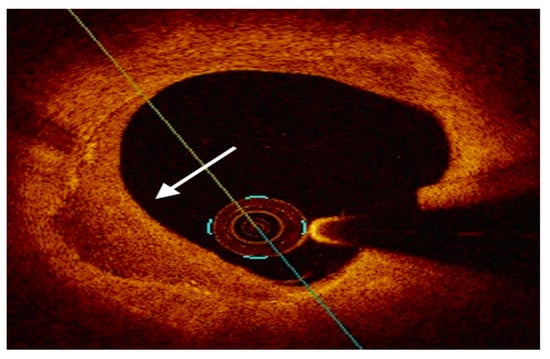

4.2. Optical Coherence Tomography